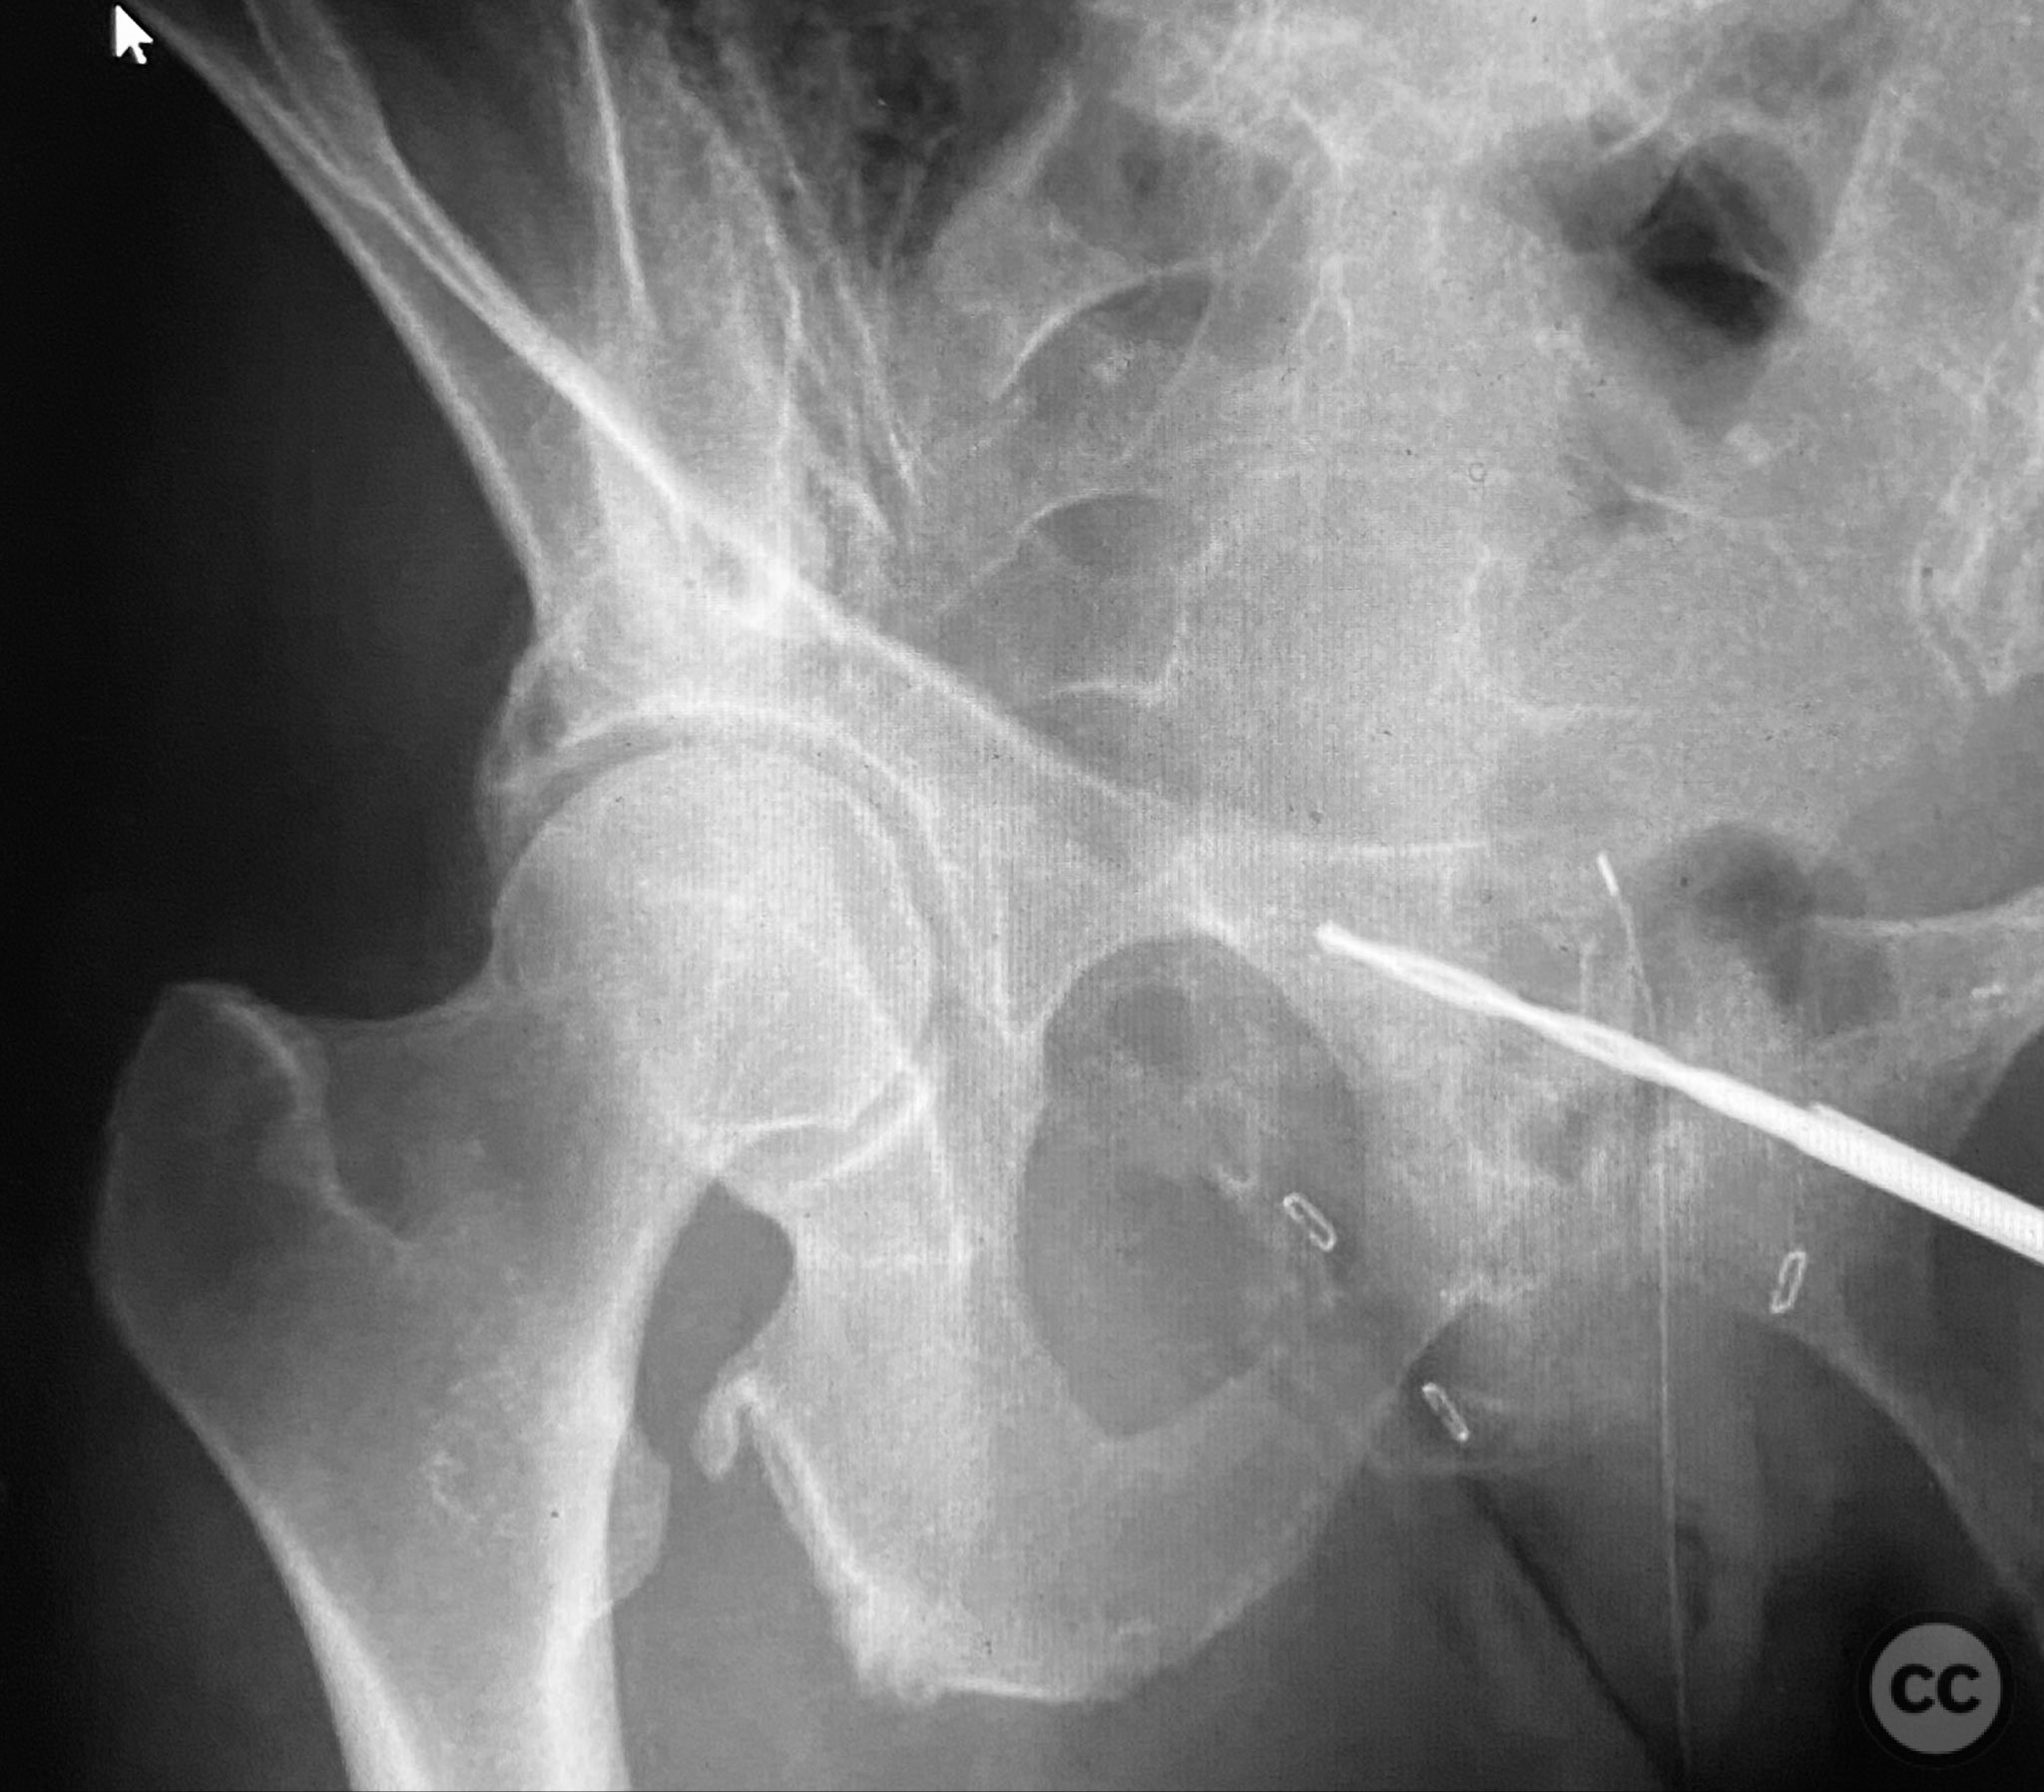

Intraoperatively, a 3.5mm drill was used through a protective sleeve to initiate the screw pathway across the superior pubic ramus. Due to poor bone quality, a 2.5mm drill was subsequently employed; however, resistance was encountered as the drill tip engaged the dense cortical apex of the anterior acetabular wall. The drill became lodged in this region. To avoid drill breakage, manual extraction using pliers was considered; however, the surgeon elected to carefully deflect and advance the drill manually, successfully completing the pathway. Screw length was measured directly from the embedded drill tip. A 4.5mm cortical screw was then inserted trans-symphyseally along the prepared medullary canal, achieving stabilization of the unstable ramus fracture. Postoperative CT confirmed appropriate screw trajectory and demonstrated the dense cortical bone at the anterior acetabular wall where the drill tip had engaged.

Postoperative protocol:   Early mobilization as tolerated with protected weight bearing, avoidance of forced hip abduction or external rotation for 6 weeks, and progressive increase in activity as pain allows.

Orthopaedic implants used:   4.5mm cortical screw